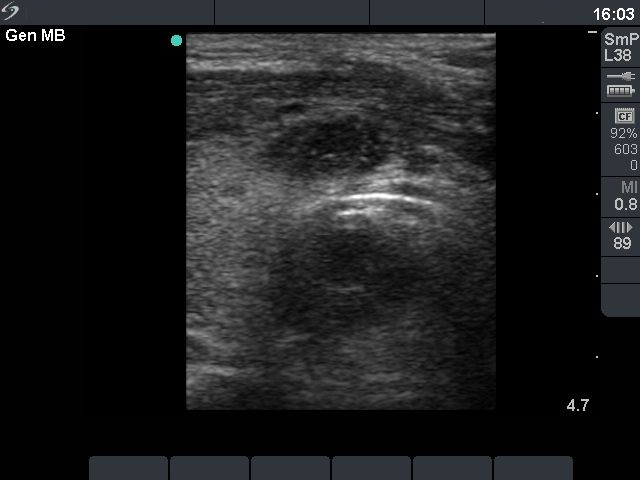

2 months later (fourth row) :

The size of the lesion decreased further and was 10x6x12 mm (width x depth x length).